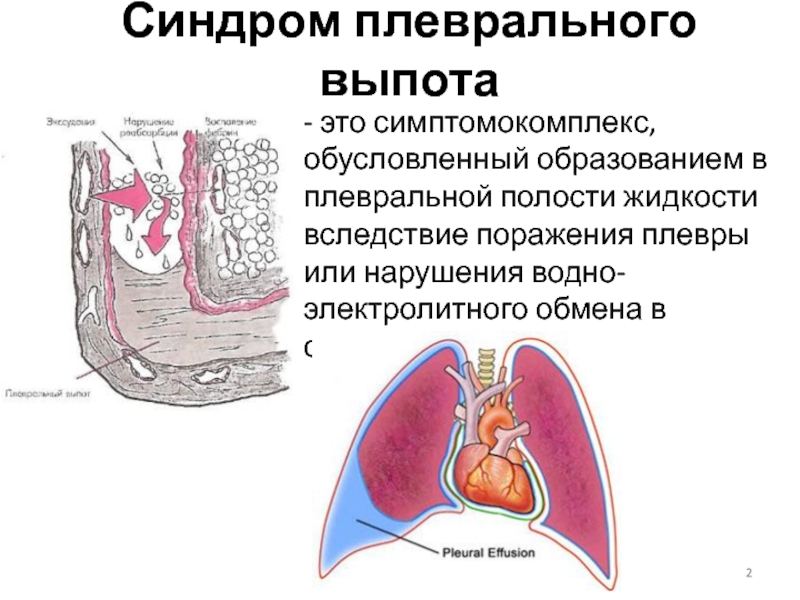

Диагностика плеврального выпота: что нужно знать